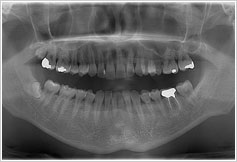

その上で、お口の中の状態を把握するためにレントゲン写真を用いて、ご希望を最大限に叶えるために、どのような治療方法があるのかをご提案させていただきます。

噛み合わせの検査、歯周病検査、レントゲン撮影、CT撮影など、患者さまの状況に合わせて必要な検査を選択し、詳しい状態を把握します。